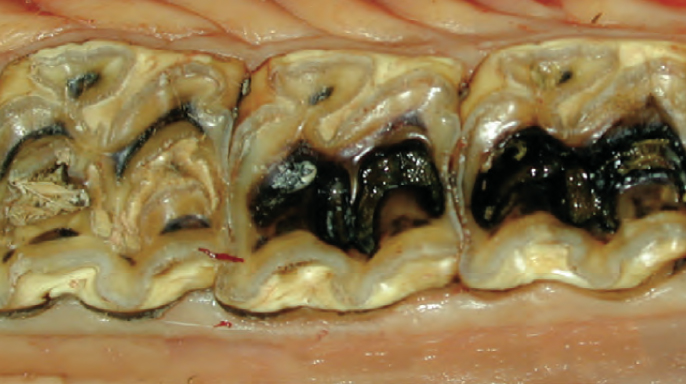

Počáteční stav dolního pravého prvního moláru